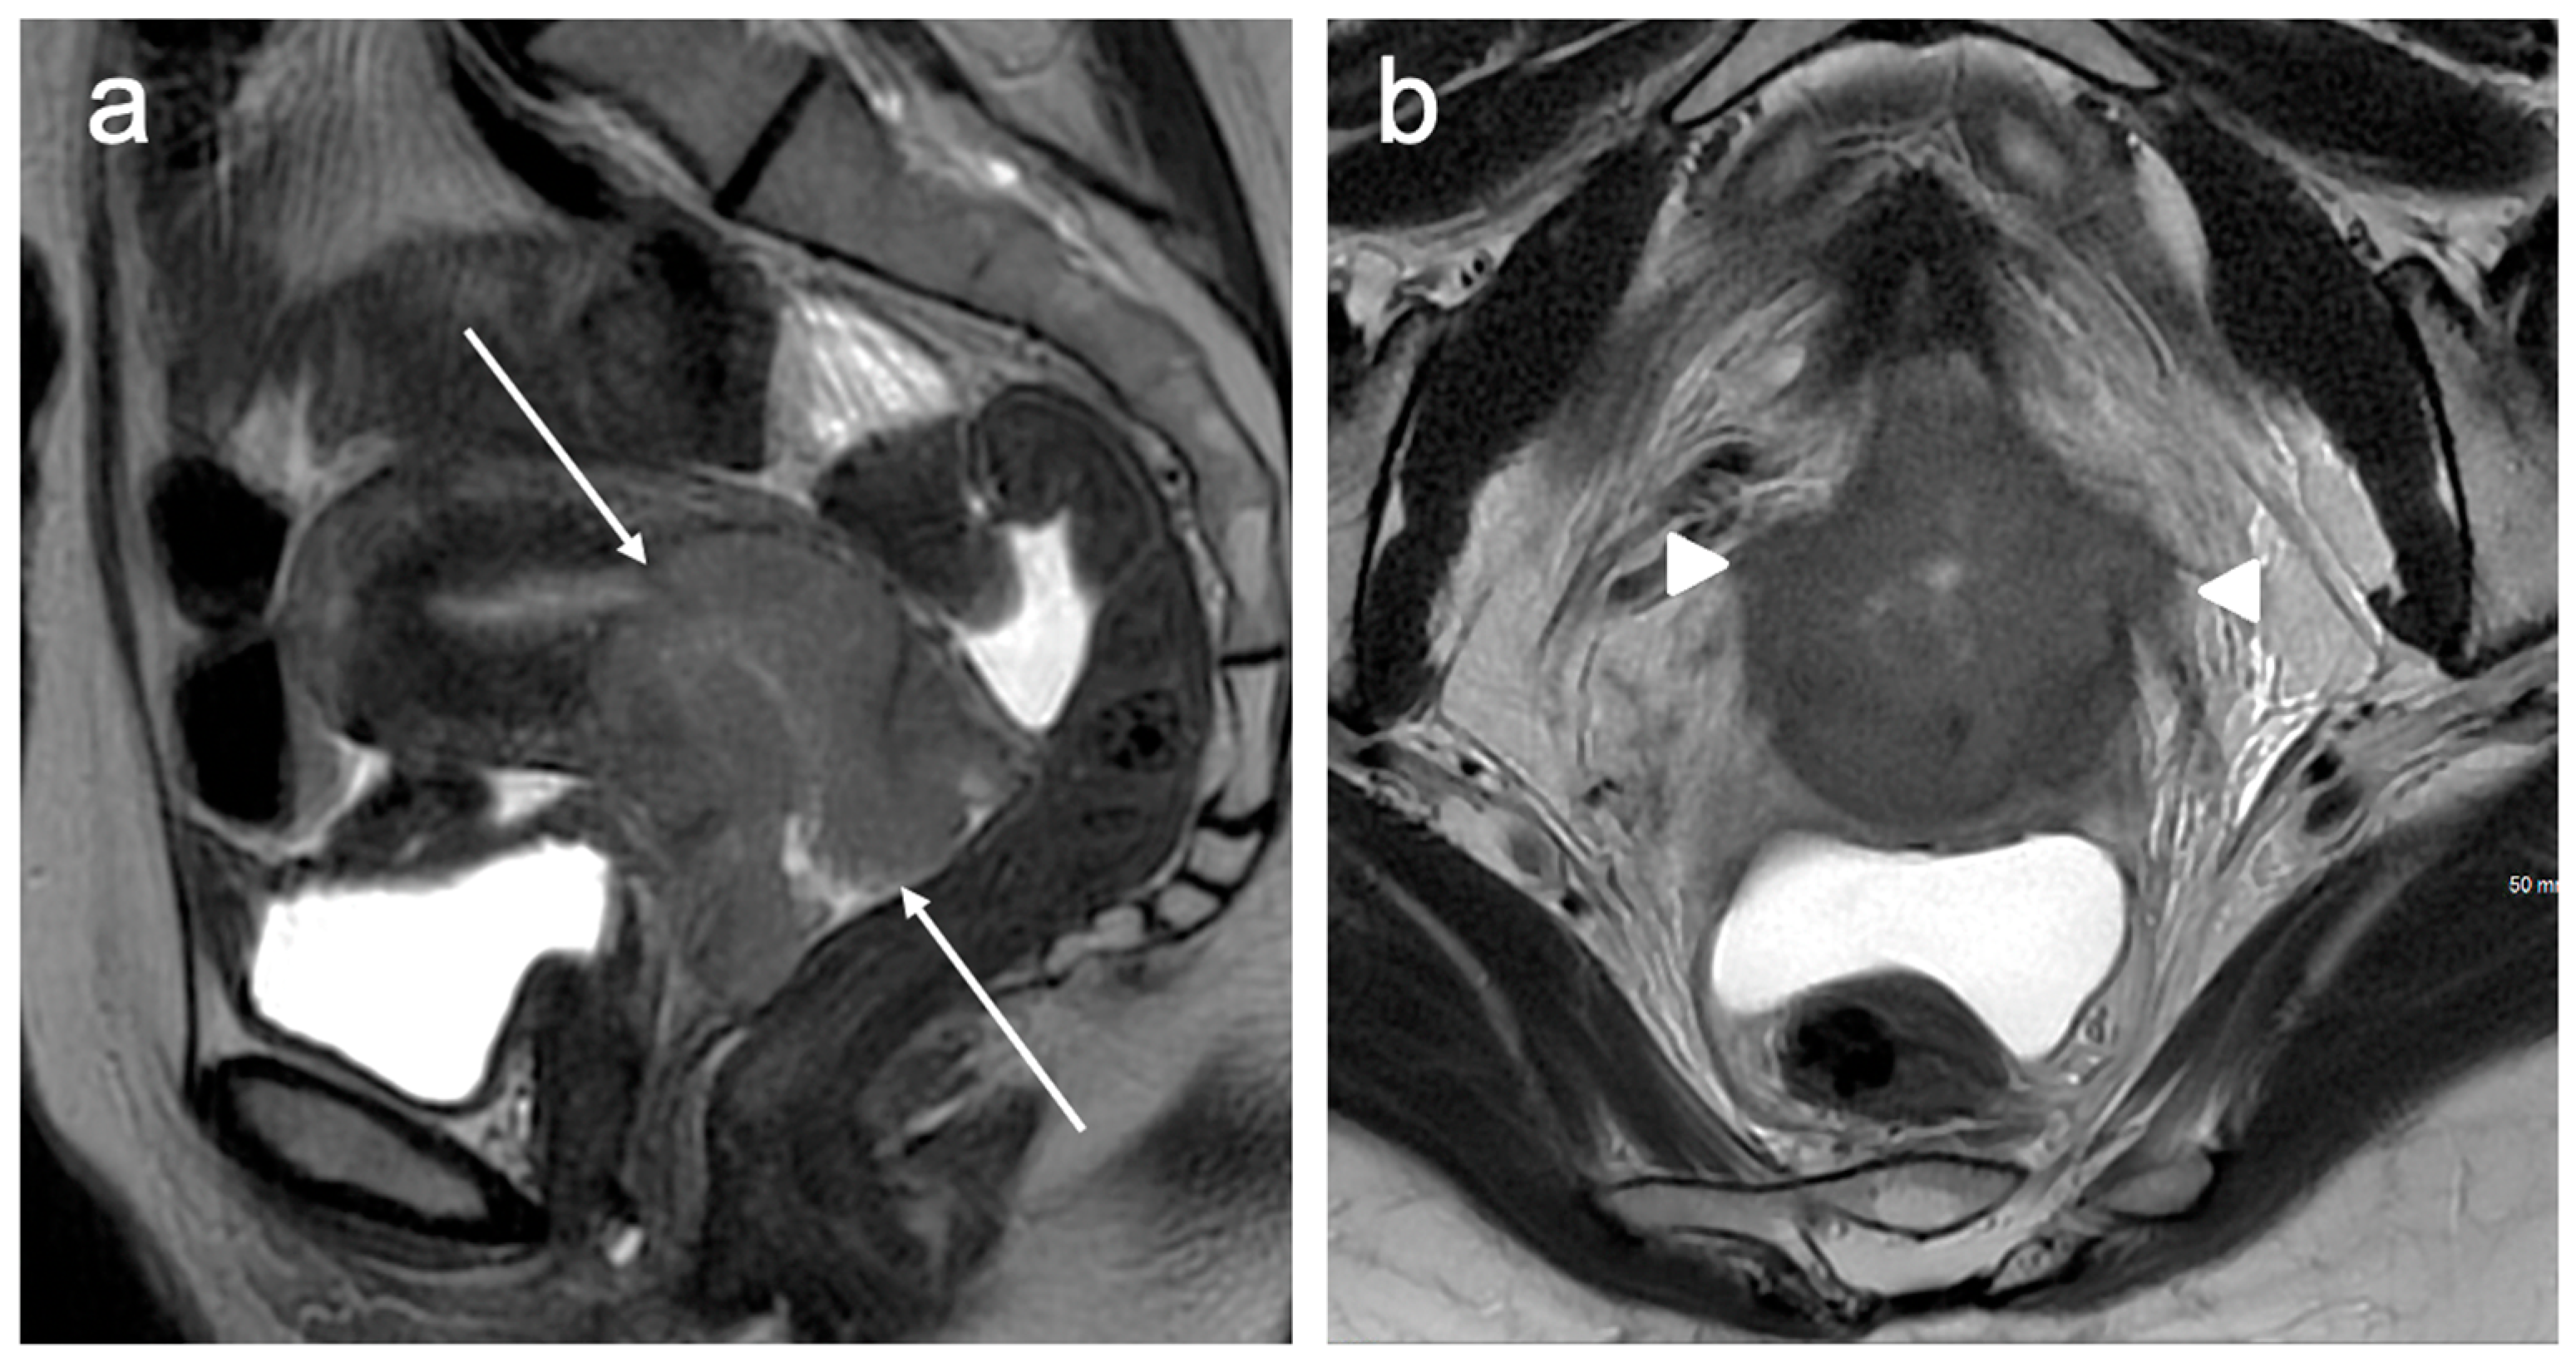

| Stage II | The cervical carcinoma invades beyond the uterus, but has not extended onto the lower third of the vagina or to the pelvic wall |

| IIA | Involvement limited to the upper two-thirds of the vagina without parametrial invasion |

| IIA1 | Invasive carcinoma <4 cm in greatest dimension |

| IIA2 | Invasive carcinoma 4 cm in greatest dimension |